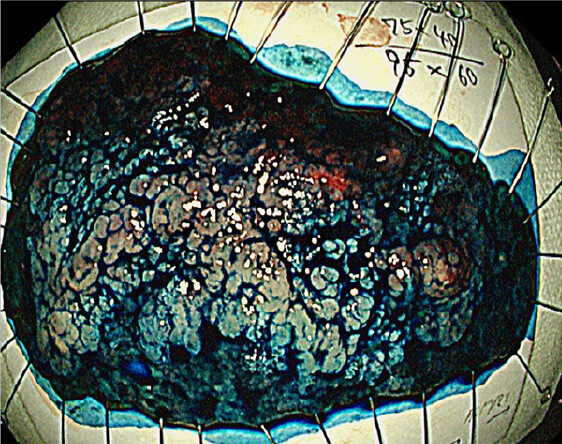

光線力学的療法(PDT)

放射線療法後の遺残再発食道癌に対する光線力学的療法(PDT)も行っており、PDTの実施可能施設は九州で4施設のみ、長崎県内では当院が唯一の実施施設となっています。

治療前

PDT

PDT 5ヶ月後